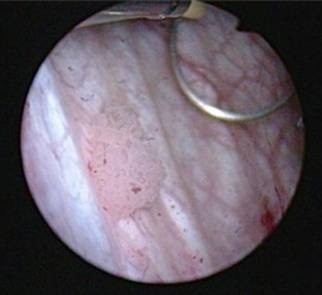

Cancer de la vessie

Traitements contre le cancer de la vessie